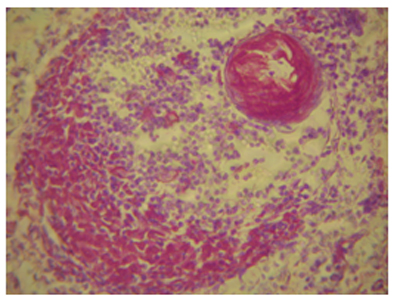

Ուսումնասիրված դեպքերից 52-ում հայտնաբերվել է փայծաղի տարբեր աստիճանի արտահայտված ամիլոիդոզ: 16 դեպքում (30,7%) սագոյի փայծաղի պատկեր է դիտվել` ավշային ֆոլիկուլներում ամի-լոիդի նուրբ դեպոզիտներով կամ ավելի ընդարձակ կուտակումներով, ընդհուպ ֆոլիկուլի ամբողջական զբաղեցումը ամիլոիդով (նկ. 3): 28 դեպքում (53,8%) դիտվել է ճարպային փայծաղի պատկեր` ամիլոիդի առատ կուտակումներով ինչպես ֆոլիկուլներում, այնպես էլ արտաֆոլիկուլային դիֆուզ ավշային հյուսվածքում, անոթների պատերում: Հայտնաբերվել է փայծաղի պատիճի լավ արտահայտված սկլերոզ և հիալինոզ, իսկ որոշ դեպքերում այն ուղեկցվել է ամիլոիդային զանգվածների կուտակումներով պատիճում (նկ. 4), իսկ 8 դեպքում (15,4%) փոփոխությունները փայծաղում միջանկյալ բնույթ են կրել:

![]() |

Նկ. 7. Արտամազանոթային պրոդուկտիվ գլոմերուլոնեֆրիտ` ուղեկցված կծիկային հանգույցների ամիլոիդոզով, հեմատոքսիլին-էոզին, x400